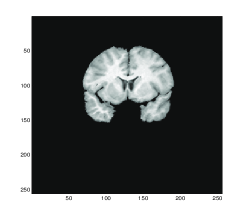

5.2 Test 2: A Pair of Brain MR Images

We take as Test 2 a pair of medical images of size 256×256256256256\times 256 from the Internet Brain Segmentation Repository (IBSR) http://www.cma.mgh.harvard.edu/ibsr where 20 normal MR brain images and their manual segmentations are provided. We choose the particular pair of individuals with different sizes of ventricle to illustrate a large deformation problem. Figure 3 shows the test images and the registration results using Gaussian curvature model. We can see that the model is able to solve real medical problems involving large deformations, which is particularly important for atlas construction in medical applications.

Figure 3: Test 2: A pair of Brain MR images. Illustration of the effectiveness of Gaussian curvature with real medical images. On the top row, from left to right: (a) template, (b) reference and (c) the difference before registration. On the bottom row, from left to right: (d) the transformation applied to a regular grid, (e) the transformed template image and (f) the difference after registration. As can be seen from the result (e) and the small difference after registration (f), Gaussian curvature can be applied to real medical images and is able to obtain good results.

Figure 4 shows the transformed template images for all four methods. We can see that Gaussian curvature gives the best result inside the red boxes in comparison with the diffeomorphic demon, the linear and mean curvature models as depicted in Figure 4 (d).